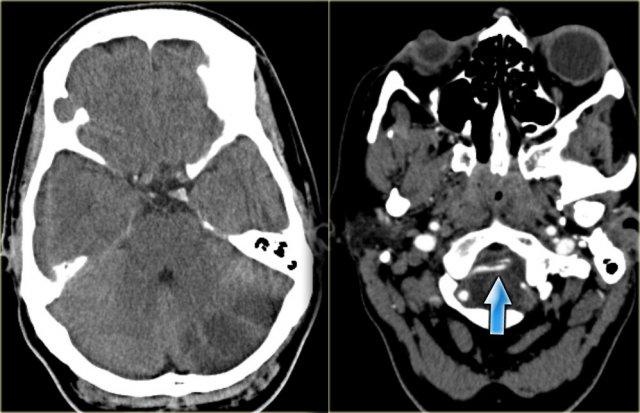

PICA

Bên trái là hình ảnh CT của nhồi máu PICA bên trái.

Lưu ý sự lan rộng về phía sau.

Nhồi máu là hậu quả của một trường hợp bóc tách động mạch (mũi tên xanh lam).

Bên trái là hình ảnh MRI của nhồi máu PICA bên trái.

Trong các trường hợp nhồi máu một bên, luôn có sự phân định rõ ràng tại đường giữa do các nhánh nhung mao trên không vượt qua đường giữa mà đi theo hướng dọc (sagittal).

Sự phân định rõ ràng này có thể không biểu hiện cho đến giai đoạn muộn của nhồi máu.

Trong giai đoạn sớm, phù nề có thể vượt qua đường giữa và gây khó khăn cho chẩn đoán.